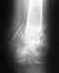

Нужен снимок, без него невозможно узнать, нужна ли операция, и если да, то какая именно.